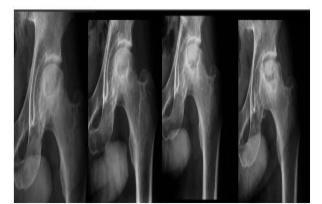

A radiologia veterinária se desenvolve a passos largos e suas aplicações têm se tornado cada vez mais presentes no dia a dia do médico veterinário. Avalie o seguinte caso clínico: Cão da raça Yorkshire, 10 meses de idade, apresentando claudicação grau 2 no membro pélvico esquerdo e dor à palpação coxofemoral esquerda. Os exames radiográficos seriados evidenciaram as alterações ósseas reveladas nas imagens abaixo.

Com base nesses dados, qual o provável diagnóstico?